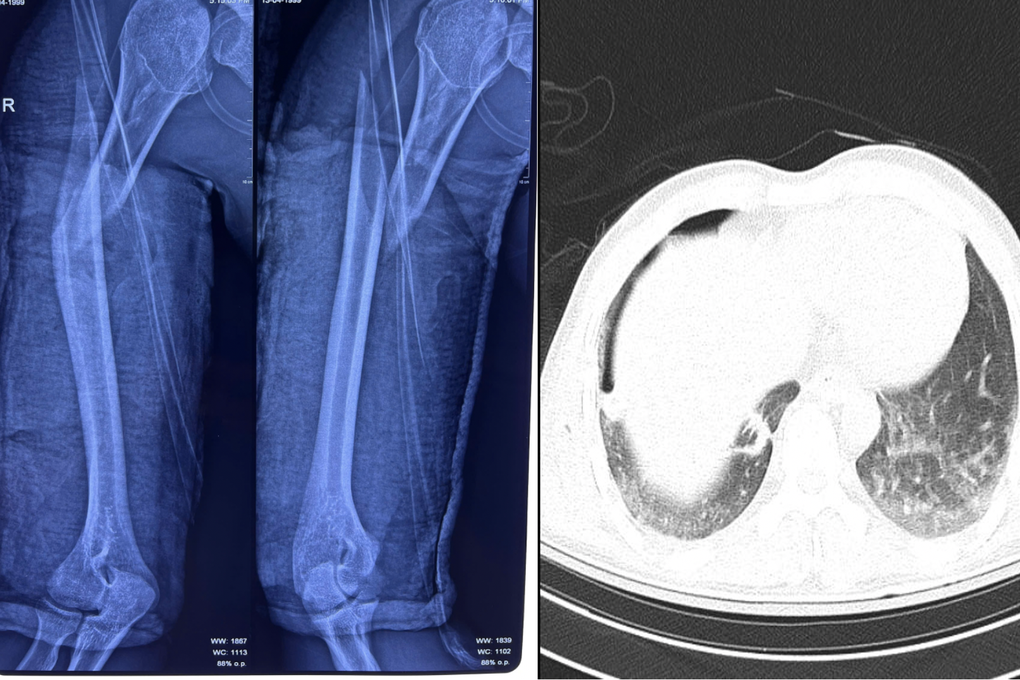

「ベッドサイドでの胸部X線検査の結果、この若者は重度の肺挫傷による右気胸を患っており、上端の複雑骨折と右上腕骨の上部3分の1の長斜骨折を患っていることがわかった」と整形外科・外傷科のソン・タン・ゴック医師は述べた。

患者の右上腕骨は完全に骨折しており、気胸の兆候が見られた(写真:BVCC)。

手術後、骨折した腕の骨はしっかりと固定されました。(写真:BVCC)